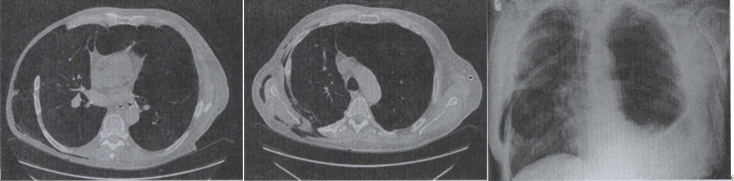

27.患者男,68岁,胸闷、气逼1年余,加重l周,右胸有手术史,结合CT图像,最可能的诊断是 ()

26.患者男,36岁,低热、咳嗽、咳痰,体重减轻,结合CT图像,最可能的诊断是 ()